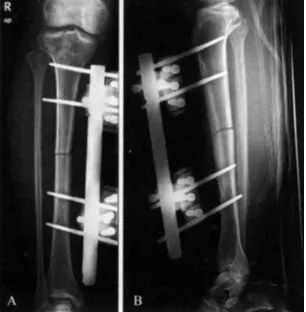

骨外固定器的临床应用还处于持续发展的阶段,除作为治疗骨折的一种方法外,还应用于治疗骨不连、膝和踝关节切除融合术、截骨矫形及肢体延长等。不同的病理情况与解剖部位需选用不同类型的外固定器。一般来说,治疗骨折时需要选用灵巧性较好的外固定器,固定后能及时行必要的再调整,以纠正对位和轴线偏差。单平面单杆或双杆外固定器,大多可满足治疗骨折的要求。

肢体延长与关节切除融合的骨外固定,对其稳定性要求则是主要的,否则难以避免由于固定刚度不足所造成的许多并发症。因此,必须根据治疗需要选择力学性能合适的外固定器。

2)置针方法:一般要求固定针应离开骨折端4~5cm左右进针,并确保针尖穿透对侧骨皮质固定。

在安装连接杆时,杆与皮肤的距离要合适,连接杆离肢体越近,骨折固定越稳定,但过近则不利于引流和针道护理,一般以2cm为宜。对稳定骨折(横行或短斜形骨折),可对骨折做加压固定,可通过微调固定杆的长度进行加压。对不稳定骨折,针组间不能加压,往往需要外固定器的原位固定,骨折端加压可借助有限内固定或附加其他固定针进行靠拢加压。

对严重粉碎性骨折或骨缺损,可延伸固定杆以维持原肢体长度,即牵伸固定。